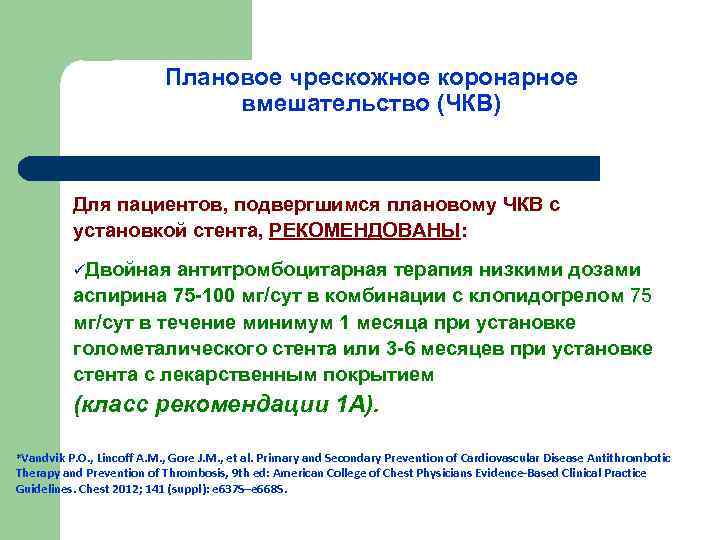

Плановое чрескожное коронарное вмешательство (ЧКВ) Для пациентов, подвергшимся плановому ЧКВ с установкой стента, РЕКОМЕНДОВАНЫ: üДвойная антитромбоцитарная терапия низкими дозами аспирина 75 -100 мг/сут в комбинации с клопидогрелом 75 мг/сут в течение минимум 1 месяца при установке голометалического стента или 3 -6 месяцев при установке стента с лекарственным покрытием (класс рекомендации 1 А). *Vandvik P. O. , Lincoff A. M. , Gore J. M. , et al. Primary and Secondary Prevention of Cardiovascular Disease Antithrombotic Therapy and Prevention of Thrombosis, 9 th ed: American College of Chest Physicians Evidence-Based Clinical Practice Guidelines. Chest 2012; 141 (suppl): e 637 S–e 668 S.